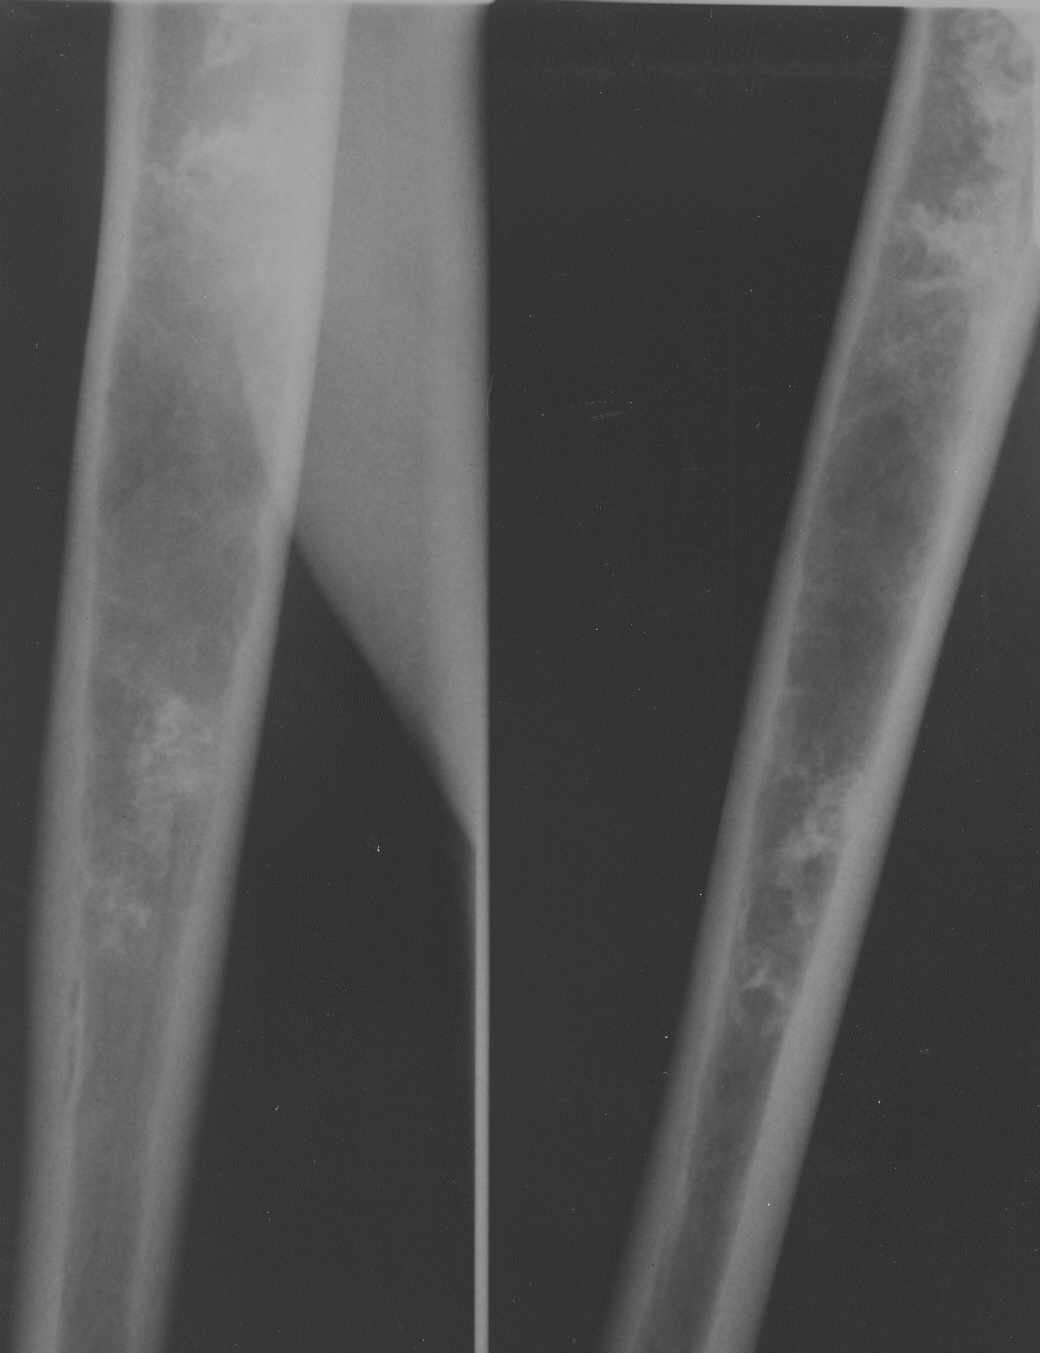

Патология плечевой кости

Обратился пациент с жалобами на боли в области плечевого сустава.

Боли беспокоят при движениях (поднятии руки, заведении руки за спину). В покое боли не беспокоят. Кроме болей ни субъективно, ни клинически никаких данных. Получены вот такие рентгенограммы: